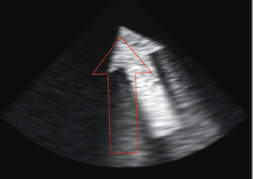

BEDSIDE ECHOGRAPHY MODULE:

The Bedside Echocardiography Module incorporates 10 hands-on tasks and clinical cases, accompanied by comprehensive didactics.

The simulation environment combines high level of realism with advanced educational aids, featuring:

- Step by step dedicated Bedside Echocardiography tasks promoting self learning of the complete protocol as well as anatomy structures recognition.

- Featuring basic standard views complemented by more challenging views such as suprasternal, IVC, apical 2 chambers, apical 3 chambers and more.

- Diverse virtual patient cases taking after real patients, ranging from normal, through slightly abnormal to distinct pathologies.

- Incorporated ECG, Cine loops recordings, calliper measurements and more.

- The clinical cases present scenarios and complaints such as chest pain, mild to severe dyspnea, diverse arrhythmia, diaphoresis, weakness and more.

- With findings such as: normal heart, mitral regurgitation, aortic dissection, pericardial effusion, pulmonary embolism (PE), dilated cardiomyopathy (DCM), Myocardial infarction (MI), tamponade and more.